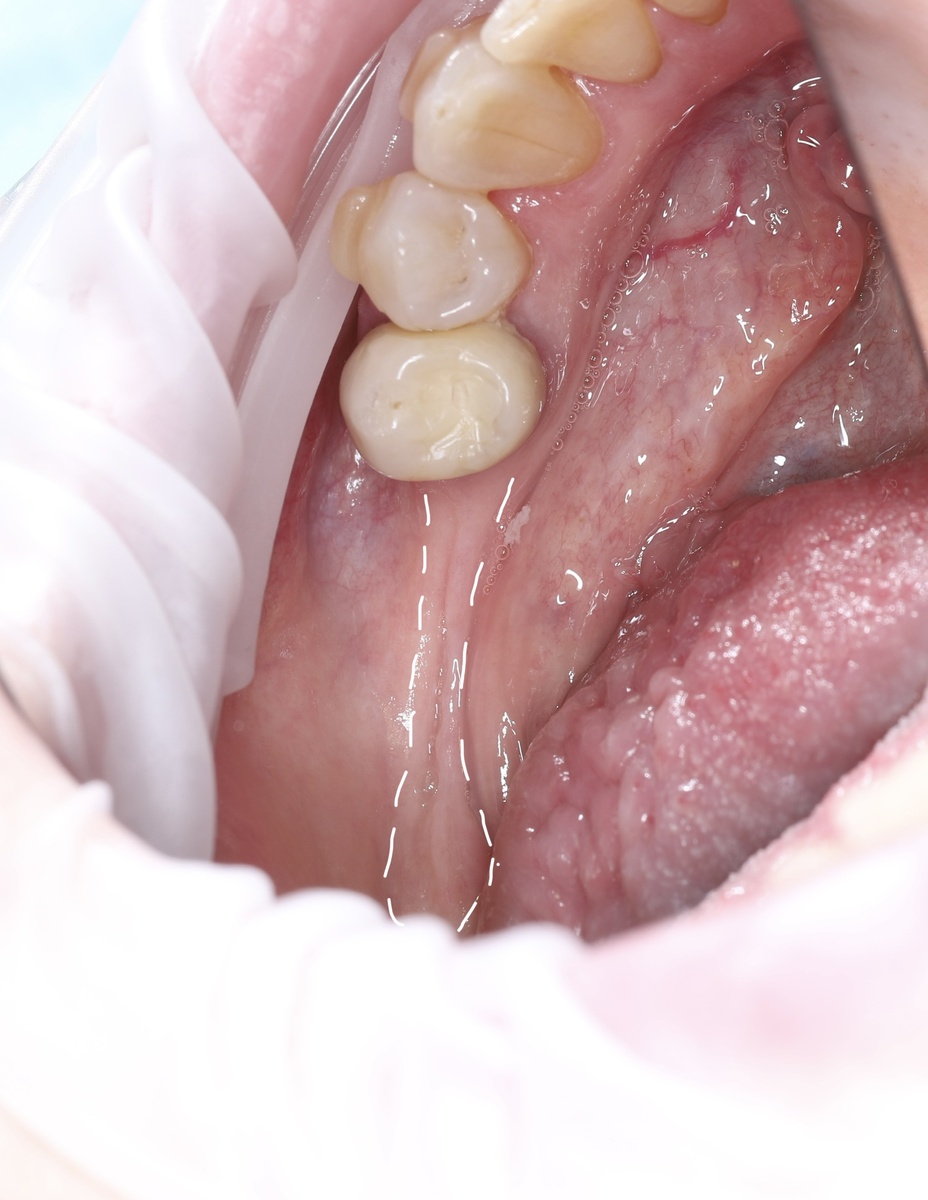

В данном случае фенотип десны тонкий (значит трофики/питания мало) , костная ткань с выраженным кортикальным слоем и атрофия костной ткани + десны выраженная, вредных привычек нет:

И от той слизистой, которая нужна для имплантатов остаётся тонкая полоска:

Приступаем к исправлению ситуации, проводим операцию по апикальному смещению подвижной слизистой и пересадке трансплантата с нёба: